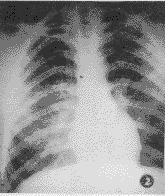

图1 男,20岁,急性炮烟中毒后约2 h入院急诊摄片,示两肺弥漫性分布的云絮状,小斑片状模糊阴影,病灶以肺尖至肺底,内带至外带均有分布,以中外带为甚。分别于第3 d及第6 d经透视复查见其吸收迅速,于第3 d已显著吸收,于第6 d见其已恢复正常 图2 男,18岁,系急性炮烟中毒后约2 h入院急诊摄片,示右肺中下野局限性小斑片状,密度较淡的云絮状阴影,左肺中野亦可见,且以中外带明显 图3 系图2同一病例,于入院后经治疗后第5 d复查片,可见其病变已基本吸收

急性炮烟中毒肺部病变X线征象主要取决于吸入的量、浓度和作用的时间。轻中度中毒者可无异常X线征象,或仅示肺纹理增多、紊乱;而临床仅轻微的头痛、头晕、乏力;本组即有6例。吸入的量多、浓度高而致重度中毒者,其X线示:①局限性小斑片状、云絮状影;②呈弥漫性肺水肿征象,分别占3例和2例。而临床则进一步有呼吸困难、恶心、呕吐、嗜睡;咽部充血、口唇和甲床呈樱桃红色。值得注意的是本组尚有1例(图1),并无明显临床症状和体征,而X线却示:弥漫分布于两肺的小斑片状,云絮状,且外中带多见的弥漫性肺水肿征象。此与Diller氏提出的肺水肿最早的X线征象可在无症状的中期出现相符[3]。故此X线可及早发现其肺水肿改变,利于临床及时防止肺水肿的发展。

轻者多无特异X线征象;而其重度中毒者所致肺水肿征象与其它原因所致者却有所不同:本组病例并未见急性肺水肿的典型征象——“蝶翼征”[4],而是呈弥漫分布的小斑片状、云絮状、模糊的阴影,且以中外带为多。此与Frendlich提出的吸入化学物质所致的肺水肿,病灶分布周围性多于中心性相同[5]。此亦是与流体静力性肺水肿的不同之处。概而言之,其特点为:密度淡而均;可合并间质影(因炮烟中所含的NO2所致的支气管及其周围炎);病灶呈弥漫分布;动态变化快,透视或摄片证实经治疗后可于短期内吸收(图2,3)。